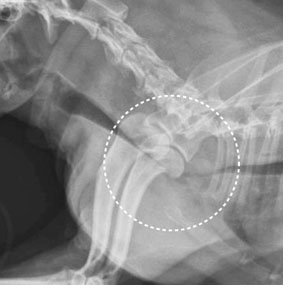

X線検査をします。病状がはっきりと現れている犬の場合には、はっきりと気管が扁平になって狭くなっていることがわかります。